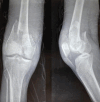

Introduction: Distal femur fractures are mostly caused due to vehicular injuries in the middle-aged population. Operative treatment has been preferred with open reduction and internal fixation in these fractures. Due to the availability of anatomical locking compression plates (LCPs), better results and improved functional outcomes have been observed. This study aims to observe the surgical outcome of distal femur fractures operated with an anatomical LCP.

Materials and methods: A prospective study was carried upon 48 patients with 40 male and 8 female patients having fractures of the distal femur. The mean age of presentation was 40.6 years. Thirty of them had vehicular injuries and 18 had a history of fall. Open fractures were seen in 22 patients and associated ipsilateral limb injuries were seen in 16 and contralateral limb injuries were seen in 8 patients. The patients were treated with anatomical LCP. The lateral approach was used in all cases for my study.

Results: The mean follow-up in the present study was 6 months. All fractures were united with a mean union period of 18.2 weeks. At final follow-up, fixed flexion deformity was seen in 25% of the patients. There were 16 cases of infection with 2 being a superficial infection treated conservatively and 14 cases having a deep infection treated with debridement and antibiotics. 2 cases of nonunion, 4 cases of malunion and 4 cases of delayed union were observed. 16 cases develop joint stiffness. 16 cases also developed limb shortening and 10 had fixed flexion deformity and 8 had varus deformity. At the time of final follow-up through "SCHATZKER AND LAMBERT SCORING SYSTEM," satisfactory outcomes were achieved in 50% (20.8%excellent and 29.2% good) of the patients.

Conclusion: Distal femur fracture treated with anatomical LCP needs careful anatomical reduction, rigid fixation and early knee mobilisation and weight bearing on signs of healing with an early presentation to the hospital from the time of injury were the essential factors in achieving better outcome for the patient.